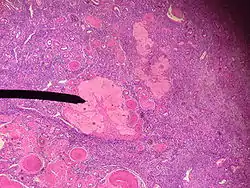

Human corpus albicans | |

The corpus albicans (Latin for "whitening body"; also known as atretic corpus luteum, corpus candicans, or simply as albicans) is the regressed form of the corpus luteum. As the corpus luteum is being broken down by macrophages, fibroblasts lay down type I collagen, forming the corpus albicans. This process is called "luteolysis". The remains of the corpus albicans may persist as a scar on the surface of the ovary.

The corpus luteum normally grows to about 1.5 centimeters in diameter, reaching this stage of development 7 to 8 days after ovulation. Then it begins to involute and eventually loses its secretory function and its yellowish, lipid characteristic about 12 days after ovulation, becoming the corpus albicans.[1] In the ensuing weeks, this is replaced by connective tissue and over months is reabsorbed.[2]